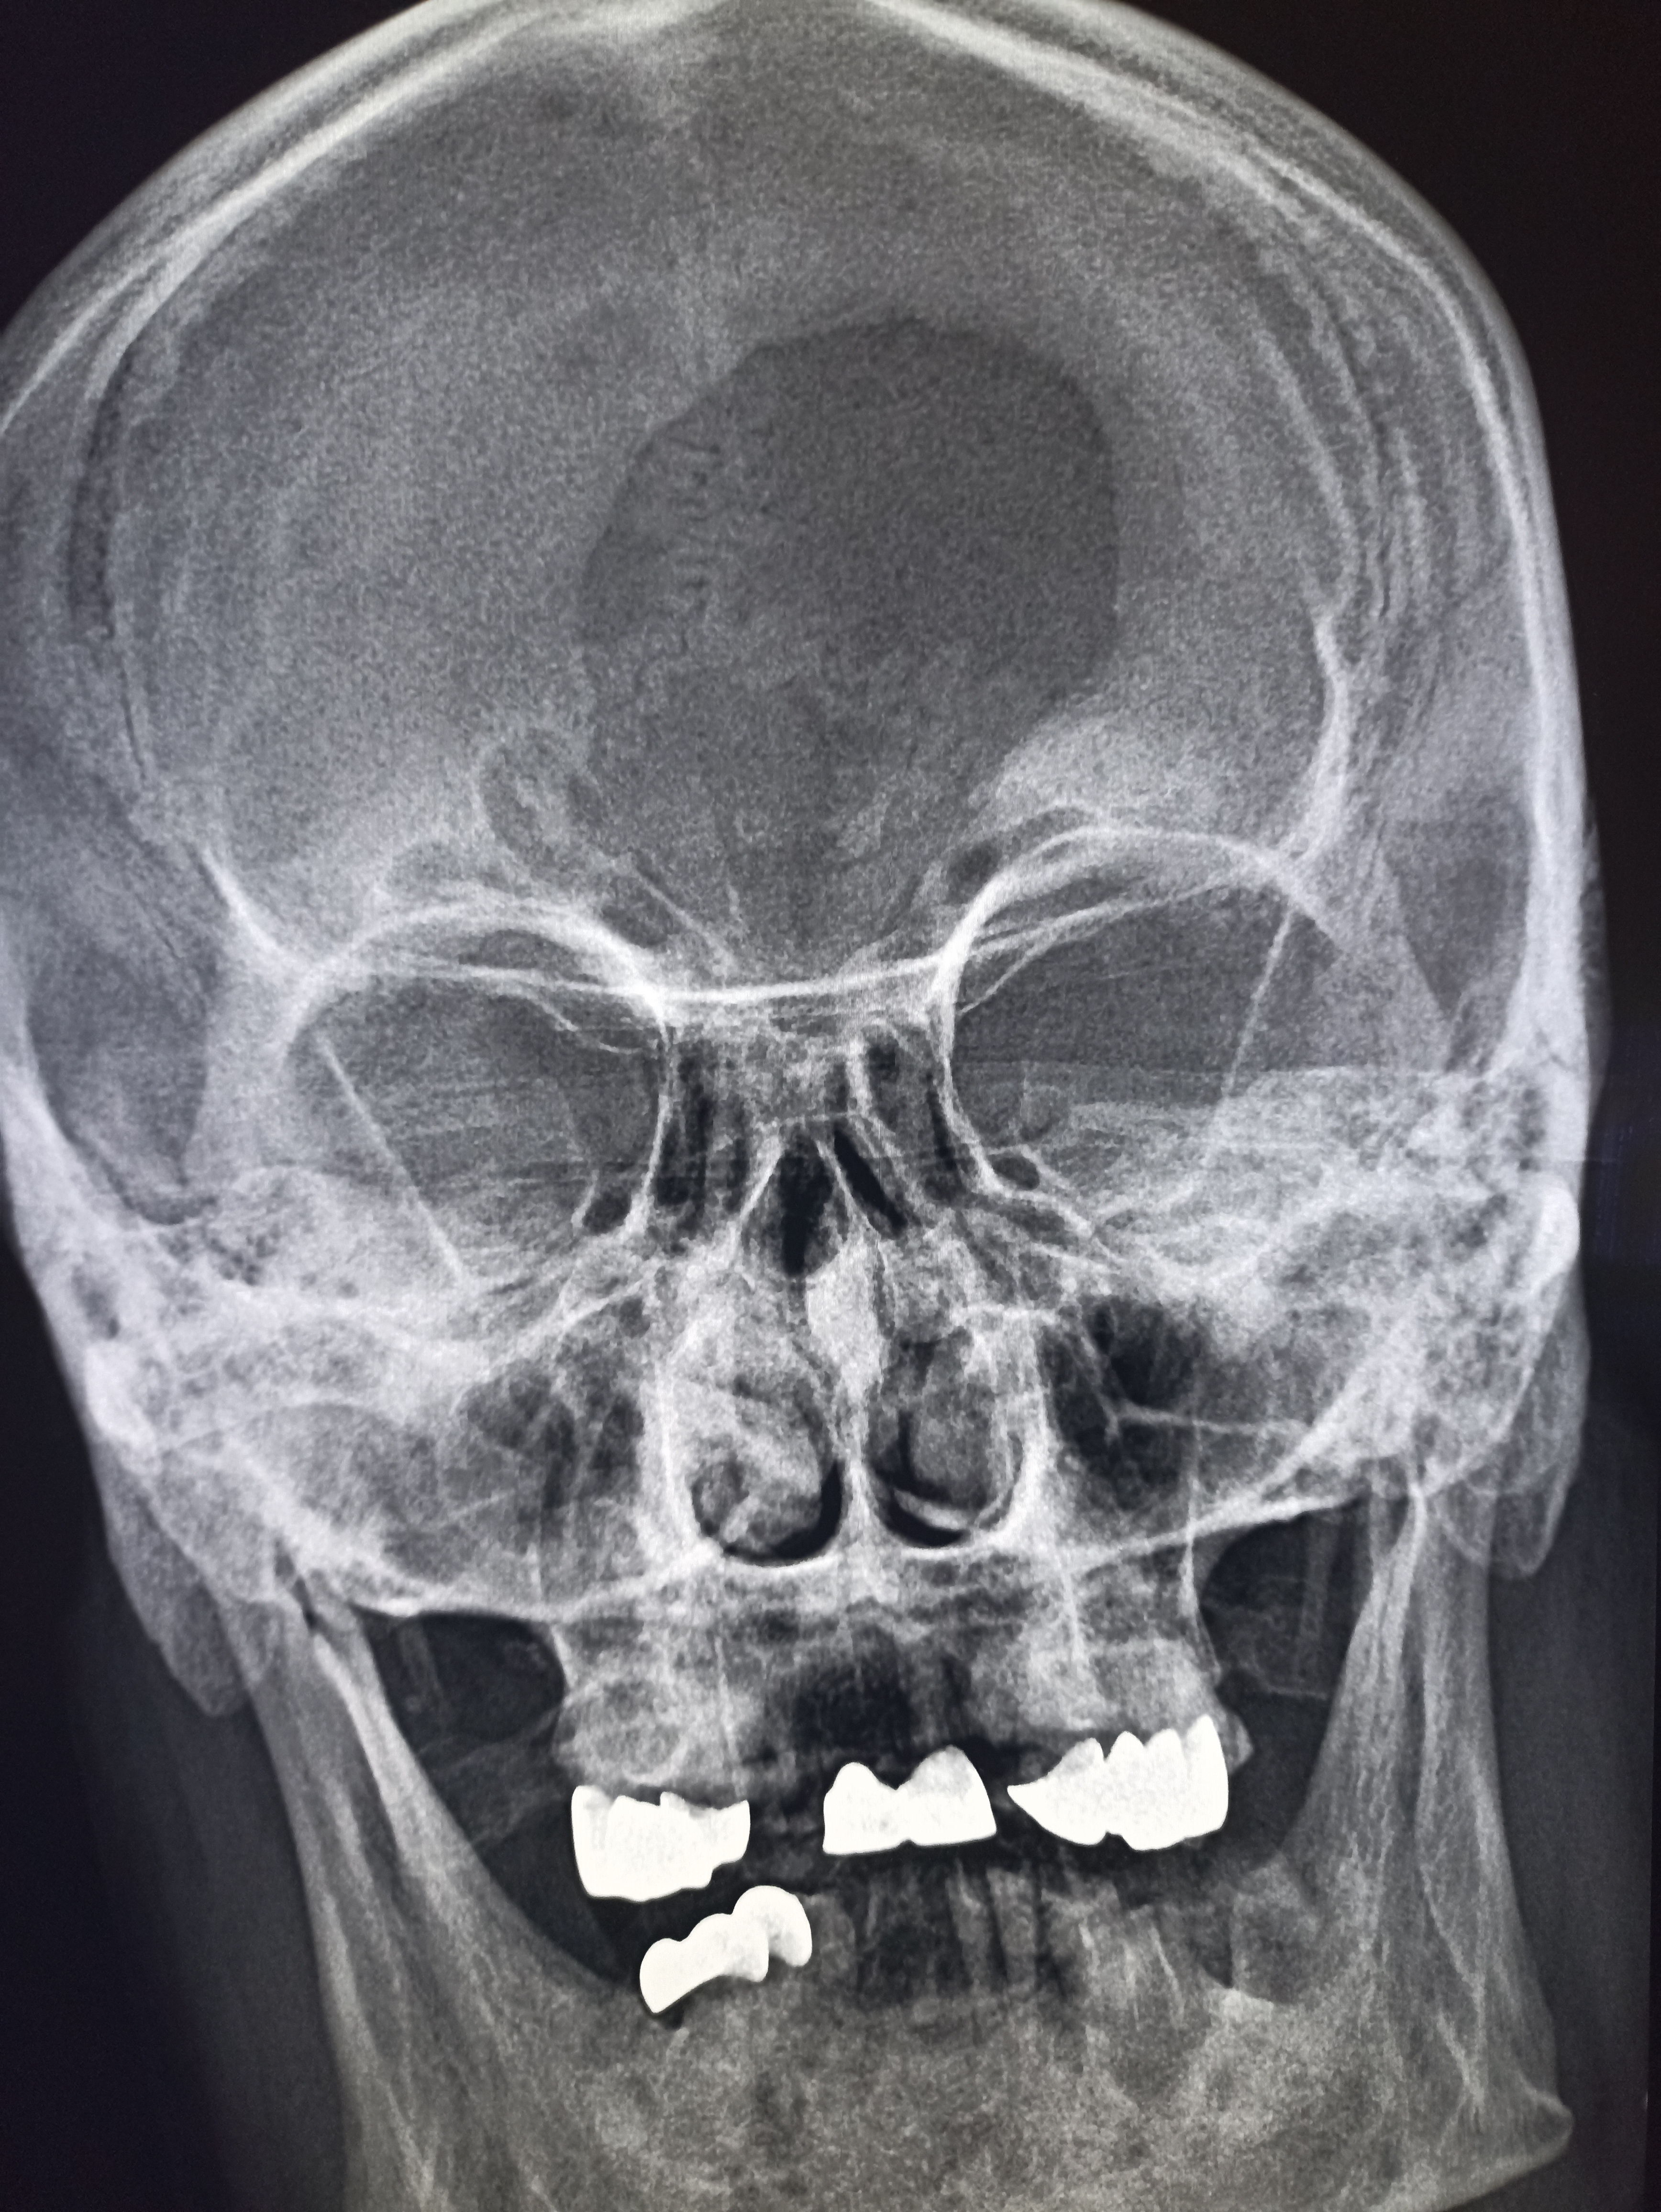

IMG20251016110751.jpg

Где пиздецомы?

IMG20251016113543.jpg

Чо тут-у нас?

>>325600523

справа гайморит

>>325600669

Нет гайморит же